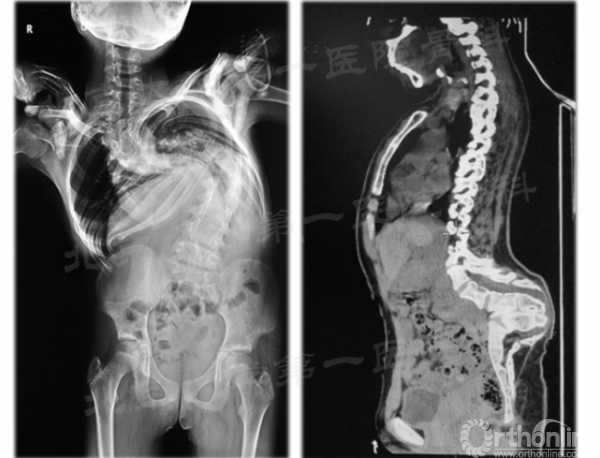

典型病例3

14岁男性,神经纤维瘤病伴T7半椎体畸形,全身多发牛奶咖啡斑。重度限制性通气功能障碍。牵引前肺潮气容积0.42 L,最大肺活量1.27 L,用力肺活量1.26 L,FEV1/FVC 为83.67%,最大通气量41.44 L/min,DLCO SB为5.19,牵引58日后身高增高22cm,肺潮气容积0.54 L,最大肺活量1.6 L,用力肺活量1.6 L,FEV1/FVC 为93.86%,最大通气量57.36 L/min,DLCO SB为5.64,肺功能较牵引前明显改善。牵引后矢状面矫形率为55.2%,矫形术后冠状面总矫形率64.0%,矫形术后冠状面总矫形率27.0% 。